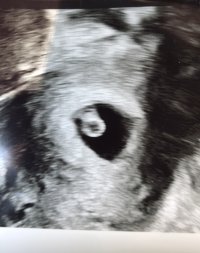

Lykke tilVæææh, måtte plutselig bytte timen min som var til torsdag, så nå blir det plutselig ultralyd i dag!!!! Om en halvtime! 7+0…. Håper på det beste. Vondt i magen.

Så braFant et lite hjerte som slovar bare ca 6+3 som kan stemme da jeg hadde sen eggløsning denne gangen.

Hun mente det hadde vært tvillinger men den ene hadde ikke utviklet seg. For det var et ekstra «hulrom» der (vet ikke hva det heter?) men hun fant ikke noe huleboer der. Skulle tilbake om to uker og sjekke at dette «hulrommet» forsvant. Noen som har vært borti lignende? Var visst ikke så uvanlig sa hun.